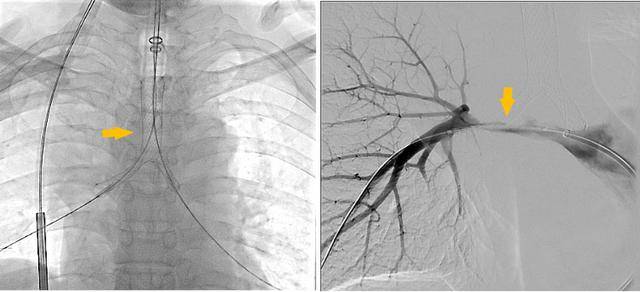

手术过程